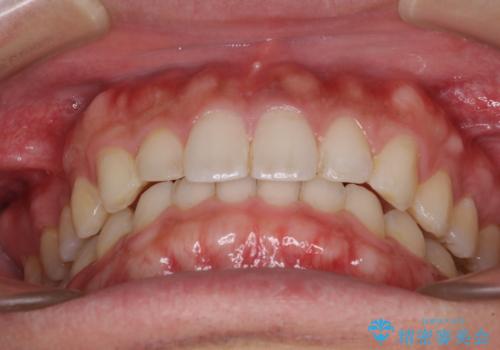

細かい隙間にものがはさまる インビザラインによる矯正治療

- 上下の前歯の隙間を気にして来院された患者様です。

インビザラインを用い、上下歯列のスペースを閉じていくこととしました。

銀行にお勤めのため、突然の転勤により通院が大変な状況となりましたが、インビザラインであれば2-3ヶ月に1度を目安に来院いただき、無事に治療を終えることができました。